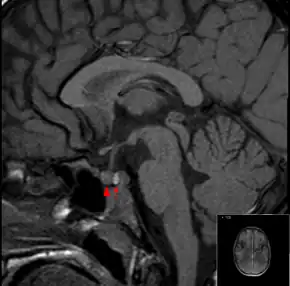

| MRI showing a pituitary macroadenoma with bleeding within the tumor resulting in pituitary apoplexy[1] | |

It is recommended that magnetic resonance imaging (MRI) scan of the pituitary gland is performed if the diagnosis is suspected; this has a sensitivity of over 90% for detecting pituitary apoplexy; it may demonstrate infarction (tissue damage due to a decreased blood supply) or hemorrhage.[6] Different MRI sequences can be used to establish when the apoplexy occurred, and the predominant form of damage (hemorrhage or infarction).[7] If MRI is not suitable (e.g. due to claustrophobia or the presence of metal-containing implants), a computed tomography (CT) scan may demonstrate abnormalities in the pituitary gland, although it is less reliable.[6] Many pituitary tumors (25%) are found to have areas of hemorrhagic infarction on MRI scans, but apoplexy is not said to exist unless it is accompanied by symptoms.[6][9]